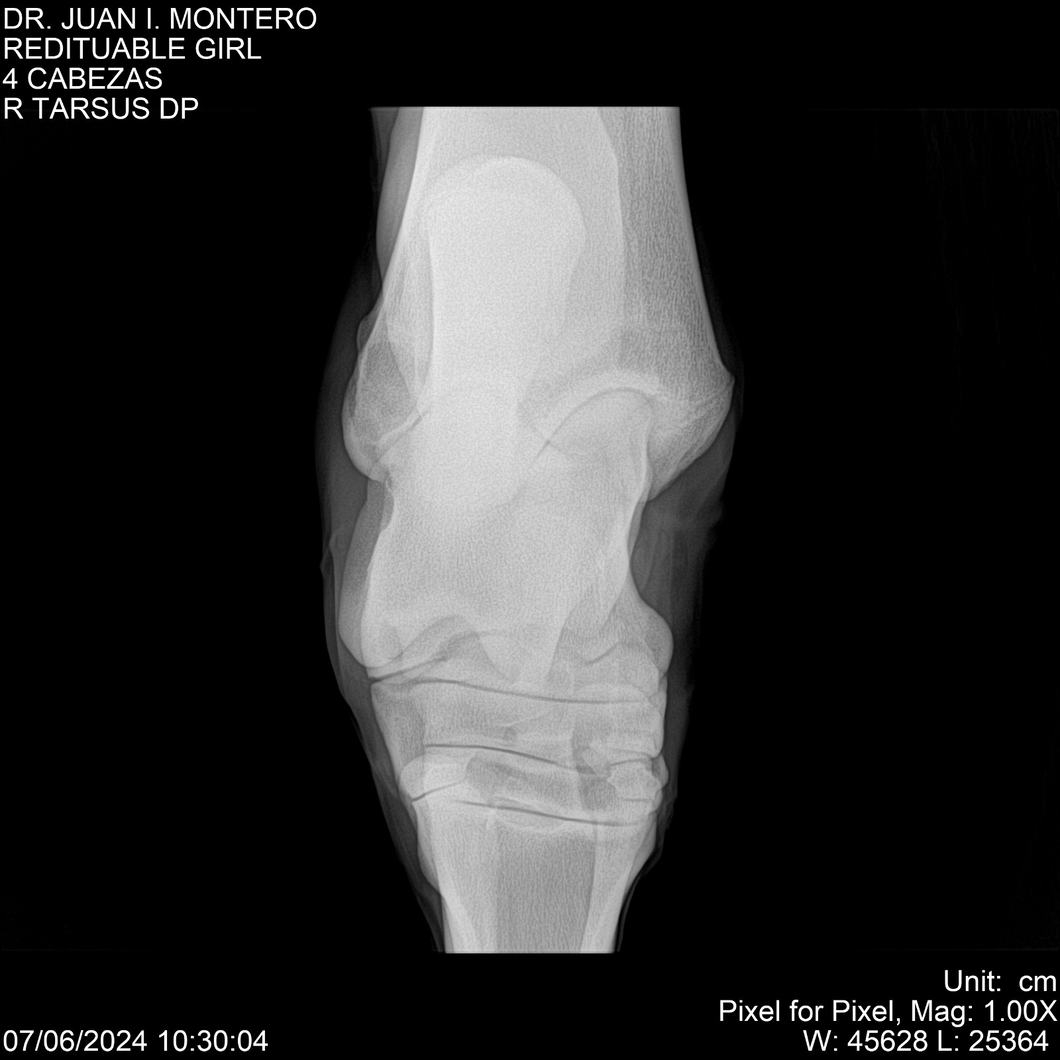

LOTE 19, REDITUABLE GIRL Lote Anterior Volver al remate Lote Siguiente Ficha Contacto Montevideo - Ficha del Lote Identificador: #281096 Categoría: Yeguarizos Montevideo - 79 Visualizaciones ClicData Contacto Empresa: Abelenda N. R., Walter Hugo Nombre*: Teléfono* : E-mail* : Mensaje Enviar Registrese gratis Este contenido Exclusivo está disponible sólo para usuarios registrados Ingresar